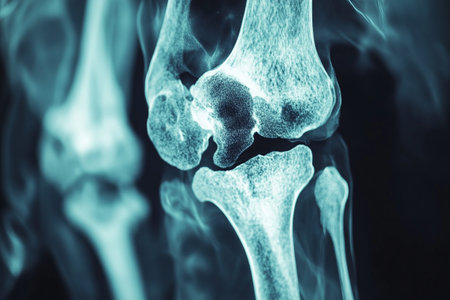

lateral view of proximal tibia fracture

x-ray image knee joint with banner design for webpage and hight quality print

X-ray of human knee joint on blue background. Medical and healthcare concept.